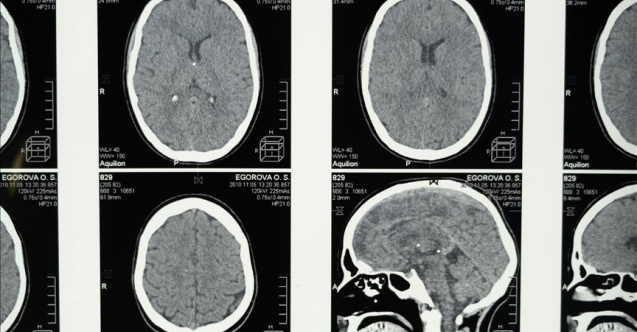

Bilim insanları, uykunun REM (hızlı göz hareketi) evresine geçmekte zorlanmanın Alzheimer belirtisi olabileceğini tespit etti

Science Daily'nin haberine göre araştırmacılar, yaş ortalaması 70 olan ve yarısına daha önceden Alzheimer teşhisi konulmuş 128 kişiyi klinikte uyutarak gözlemledi.

Araştırmacılar, deneklerin beyin dalgası aktivitelerini, kalp atış hızlarını ve solunum düzenlerini ölçtü.

Rüya görmeye başlanan REM evresine geçiş sürelerine göre denekleri 2 gruba ayıran araştırmacılar, uykuya daldıktan sonra ortalama 98 dakikadan kısa sürede REM evresine ulaşanlar "erken", yaklaşık 193 dakikadan daha uzun sürede geçenler ise "geç" grup olarak sınıflandırdı.

Çalışma sonucunda, uykunun REM evresine "geç" ulaşan kişilere, daha önce Alzheimer hastalığı tanısı konmuş olma ihtimalinin daha yüksek olduğu tespit edildi.

Uyku apnesi gibi rahatsızlıkların tedavi edilmesi ve aşırı alkol tüketiminden uzak durulması çağrısı yapan araştırmacılar, uykunun REM aşamasına önem gösterilmesi gerektiğini vurguladı.

Araştırmanın bulguları "Alzheimer Derneği" dergisinde yayımlandı.